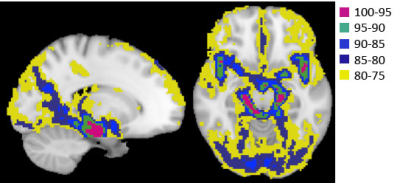

Fig. 1. ROIs determined by percentile of CBVa values in the entire brain. Higher percentile ranks indicates larger arterial vessels. For example, purple denotes the region for the top 5% of CBVa values.

Figure 1 shows ROIs determined by CBVa values (see Fig. 2A), representing different sized arteries, from large to small. Figure 2 demonstrates quantified CBVa and pulsatility maps agree strongly. The pulsatility and CBVa values from each ROI were found to be closely related with pulsatility = 0.63×CBVa (ml/100g) – 0.33 (Fig. 3). The ratio of pulsatility was exponentially decreased from large to small arteries, and the exponential decay constant varied in each individual (Fig. 4A). This was significantly decreased with mean BP and diastolic BP (Fig. 4B and 4C), but was not significantly related with systolic BP (p=0.37, R=0.24).